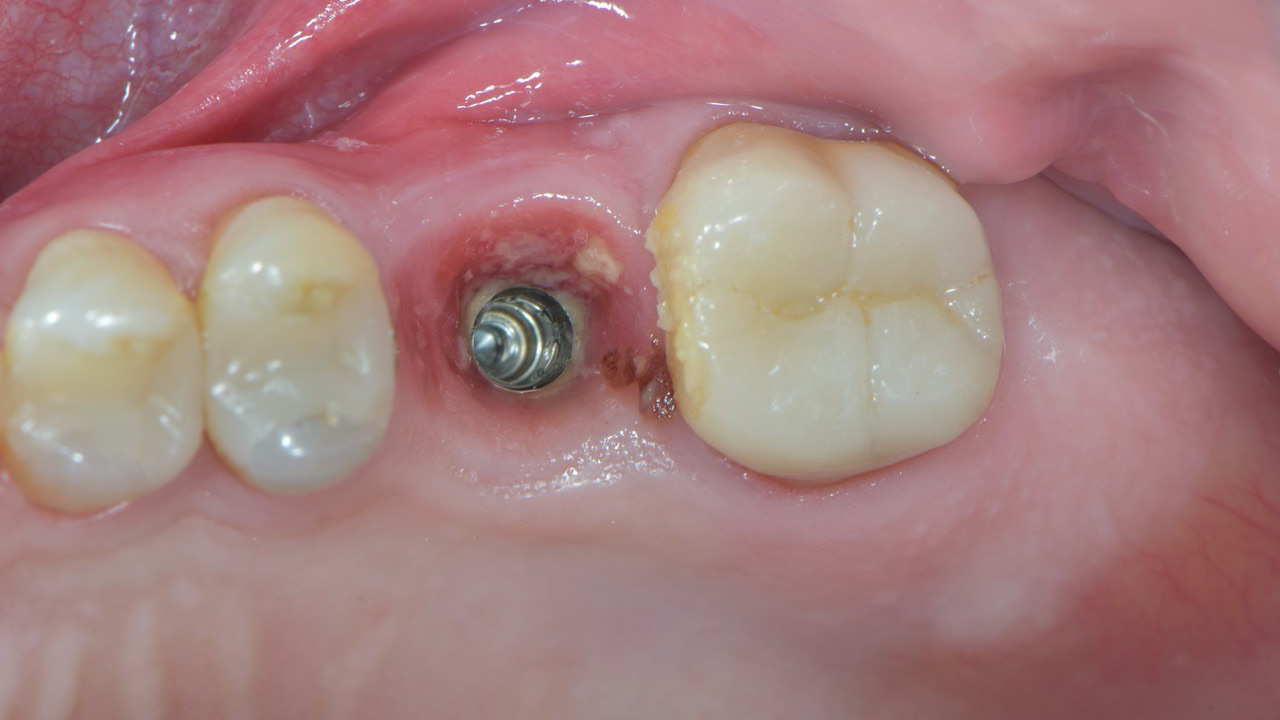

Periimplantitis stellt eine der bedeutendsten biologischen Komplikationen implantatgetragener Versorgungen dar und gefährdet langfristig die Stabilität und Prognose dentaler Implantate. Diese Falldiskussion beleuchtet Pathogenese, Risikofaktoren sowie diagnostische Kriterien und zeigt anhand klinischer Beispiele, wie ein strukturiertes therapeutisches Vorgehen entwickelt werden kann. Dabei werden sowohl nicht-chirurgische als auch chirurgische Behandlungsansätze bewertet und deren Wirksamkeit im individuellen Fall reflektiert. Die Analyse unterstreicht die Bedeutung frühzeitiger Intervention und konsequenter Nachsorge, um den fortschreitenden Knochenabbau zu kontrollieren und eine nachhaltige Implantatgesundheit zu sichern.